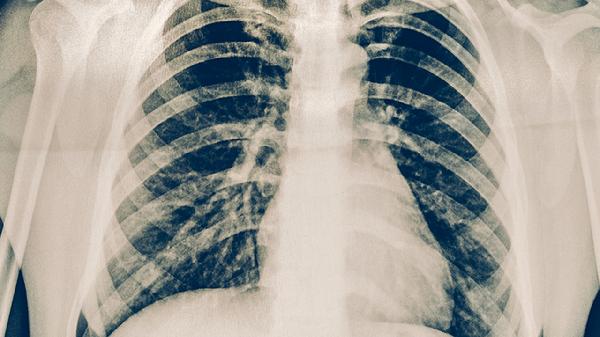

肺結(jié)核患者可以適量吃蘋(píng)果、梨、香蕉、橙子、獼猴桃等水果,有助于補(bǔ)充維生素和礦物質(zhì)。肺結(jié)核是由結(jié)核分枝桿菌引起的慢性傳染病,患者需在醫(yī)生指導(dǎo)下規(guī)范用藥,同時(shí)通過(guò)飲食輔助增強(qiáng)免疫力。

肺結(jié)核患者在飲食方面需保證充足的熱量和優(yōu)質(zhì)蛋白攝入,除水果外還可選擇雞蛋、瘦肉、魚(yú)類等食物。避免辛辣刺激性食物和酒精飲品。保持規(guī)律作息,適當(dāng)進(jìn)行散步等輕度運(yùn)動(dòng)。嚴(yán)格遵醫(yī)囑服藥,不可自行增減藥量或中斷治療。定期復(fù)查胸部影像學(xué)和痰菌檢查,監(jiān)測(cè)治療效果。注意室內(nèi)通風(fēng),咳嗽時(shí)掩住口鼻,防止疾病傳播。如出現(xiàn)藥物不良反應(yīng)或癥狀加重,應(yīng)及時(shí)就醫(yī)調(diào)整治療方案。